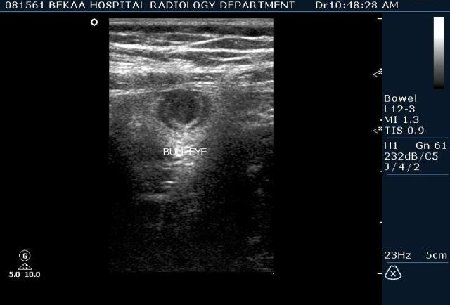

после начинаем производить хорошую компрессию датчиком попрося пациента сообщить в какой точке боль наиболее выражена; медленными движениями датчика сканируем область наибольших болевых ощущений и как правило находим утолщенный отросток. Лучше начинать с поперечной визуализации и идти к верхушке аппендикса что бы убедится что это аппендикс и он заканчивается, а не тонкая кишка (которая если и закончится то только переходя в слепую); потом надо аккуратно развернуть продольно датчик и посмотреть от верхушки аппендикса к слепой. Норма диаметра: 3-4 мм; 5-6 мм под вопросом (клиника решает; но я в катаральный аппендицит не верю); 7-8 мм и больше, не компремируемый (фиксированный отросток)-острый аппендицит! Помимо наличие утолщенного аппендикса; признака "бычьего глаза" (bull-eye sign) при поперечном сканировании; надо обращать внимание на присуствие аппендоколитов в просвете; деструкцию стенки и свободной жидкости в зоне интереса.